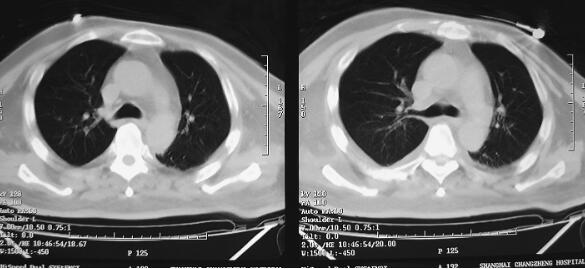

图1 CT(2月7日)结果:双下肺肺不张,双侧胸腔积液

诊治经过:患者入笔者科室后一般情况较差,血压测不出,氧饱和度84%,予以羟乙基淀粉扩容,多巴胺、去甲肾上腺素微泵维持血压,碳酸氢钠纠正酸中毒。立即予以气管插管,呼吸机辅助通气。完善相关检查:CT(图1)结果:①头颅CT平扫未见明显异常;②双下肺肺不张;③双侧胸腔积液;④肝右叶钙化灶。血常规(2月7日):WBC 20.9×109/L,N 94%。心脏彩超(2月8日):左心室舒张末内径61mm,射血分数38%。胸片(图2~图4)诊断:①双侧肺炎;②颈椎术后。先后给予头孢曲松钠和左氧氟沙星、美罗培南和替考拉宁抗感染。因痰培养鲍曼不动杆菌(2月10日),对头孢哌酮-舒巴坦钠敏感,余均耐药,故停用美罗培南,改用头孢哌酮-舒巴坦钠。多次血培养结果提示白念珠菌(2月6日、2月7日、2月9日、2月10日),对氟康唑和伊曲康唑均敏感,因为患者肌酐高,肾功能异常,故给予米卡芬净和氟康唑抗真菌治疗。患者血糖高,2月6日末梢血血糖33.1mmol/L,给予胰岛素强化治疗,但是血糖控制不佳,一直在11mmol/L以上。同时给予化痰、抗炎、保肝、营养神经、调节机体免疫、加强营养、维持内环境稳定、对症支持等治疗。